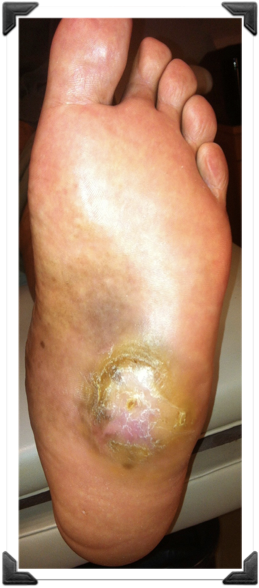

5 años Úlcera Plantar Recidivante

Dr. Luis Villanueva